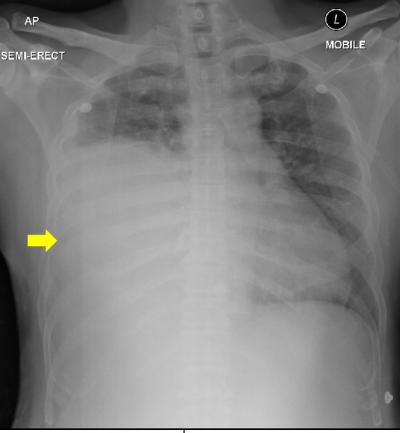

Figure 1: Chest X-ray showed the opacities of the right mid and lower zone (yellow arrow) with trachea deviated to the left.